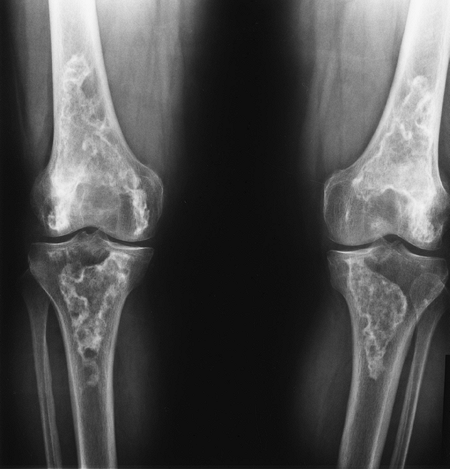

![]() |

FIGURE 5-60 Standing views of the knees demonstrating bilateral bone infarcts with dense ossification or calcification along the margins.